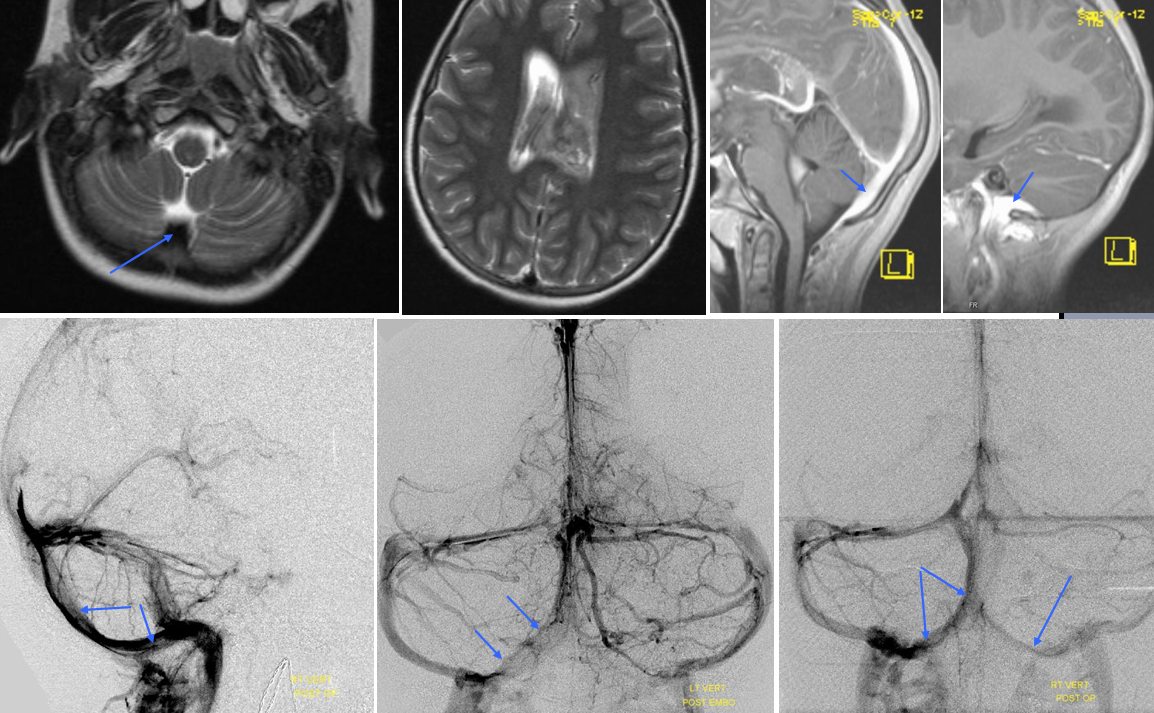

Dark blue=percallosal vein. Light blue=inferior sagittal sinus. Pink=frontal convexity vein. Orange=anterior septal vein. Yellow=thalamostriate vein. Red=Internal cerebral vein. Occipital sinus (blue arrows on the sagittal and MRI axial projections), draining into the marginal sinus (dark blue arrows on the AP projections.) The occipital sinus is more commonly seen in children.

All of the above anatomic knowledge can become very useful in evaluation of venous thrombosis. Numerous collateral pathways develop in this setting attempting to compensate for the loss. The most dramatic cases usually involve the largest channel — the superior sagittal sinus. In this case, a man presented with what initially was thought to be vasculitis-related brain hemorrhage. Subsequent workup led to an angiogram, where sagittal sinus thrombosis with extensive trans-cerebral and trans-osseous emissary vein collateral channels was seen. In retrospect, these findings were present on the patient’s earlier contrast MRI. “Venovibe” or other contrast-enhanced MR venograms can very sensitive, particularly when interpreted with the appropriate index of suspicion. Noncontrast 2-D time of flight MRV I consider to be next to useless as a problem-solving technique. Any thin-slice postcontrast T1 study is vastly superior.